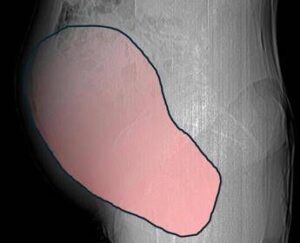

(Adnkronos) - Una donna di 69 anni ha scoperto di essere affetta da un tumore ovarico di dimensioni eccezionali, paragonabili...